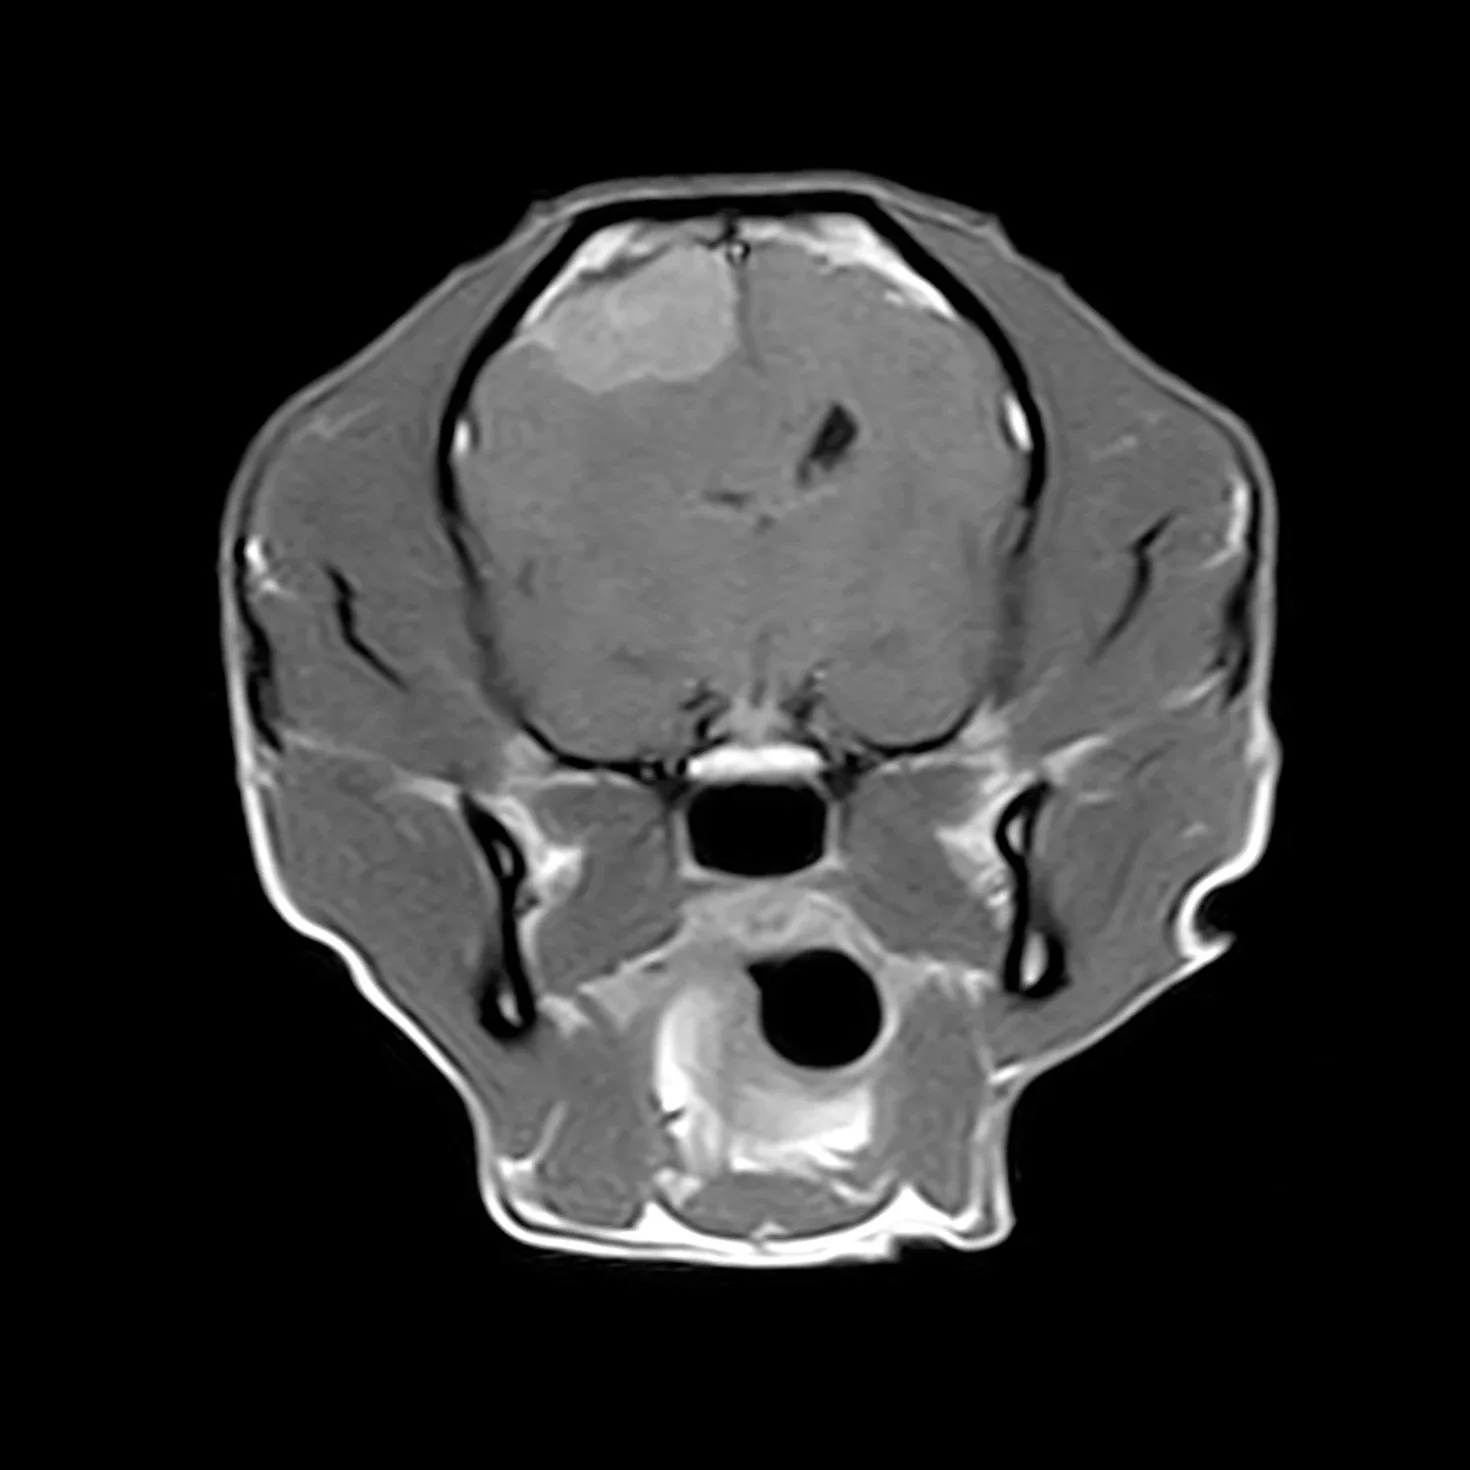

Successivamente alla visita, dopo aver effettuato esami e approfondimenti con ecografie e quanto necessario in genere, per effettuare la diagnosi ,si procede all’esecuzione di  un esame di risonanza magnetica nella sede di interesse ( encefalo o colonna vertebrale).

Con questa procedura chirurgica si eseguono interventi alla colonna vertebrale per la rimozione di ernie del disco che portano alla paralisi degli arti.

In caso di ernie del disco la procedura è molto urgente e se eseguita nei tempi previsti permette la guarigione del paziente nel 98% dei casi.

E’ possibile altresi rimuovere neoplasie esterne al midollo  ( lesioni intradurali o extradurali) ed in taluni casi selezionati  si possono rimuovere neoplasie encefaliche (meningiomi) .